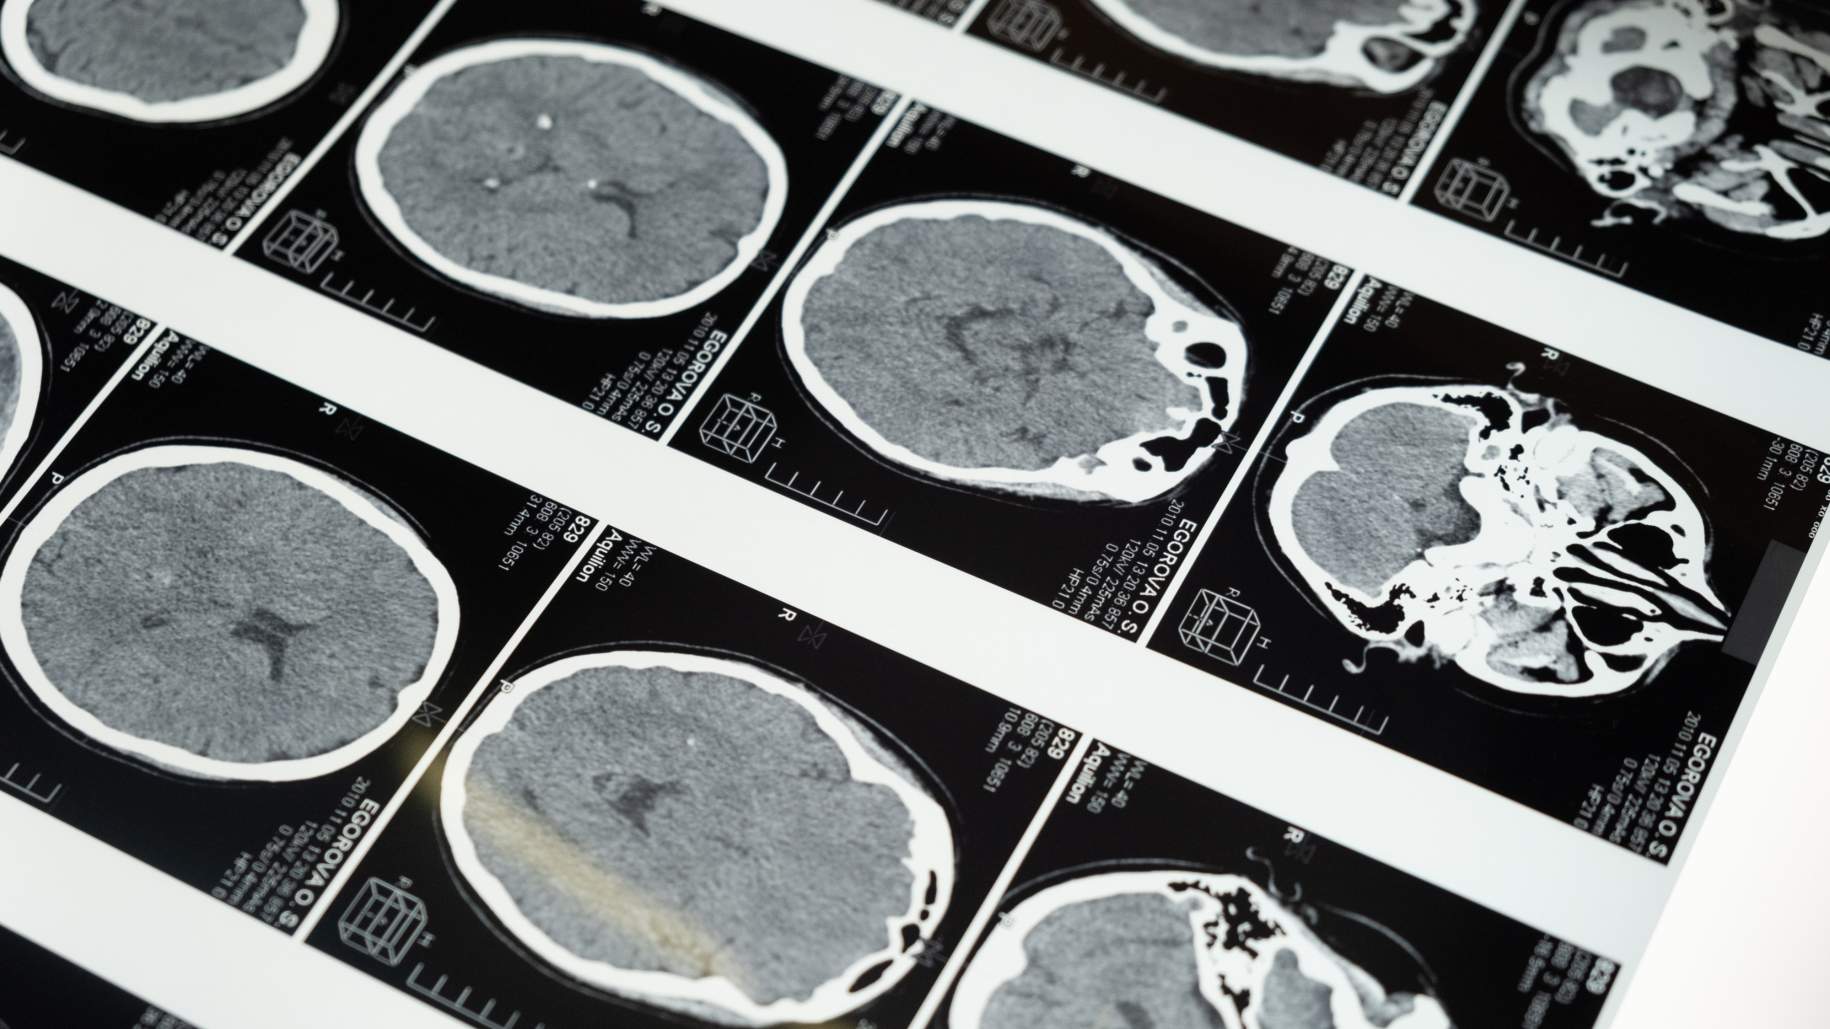

- اختبارات التصوير: قد تكون الأورام القحفية البلعومية مرئية في اختبارات التصوير مثل التصوير بالرنين المغناطيسي والأشعة المقطعية.